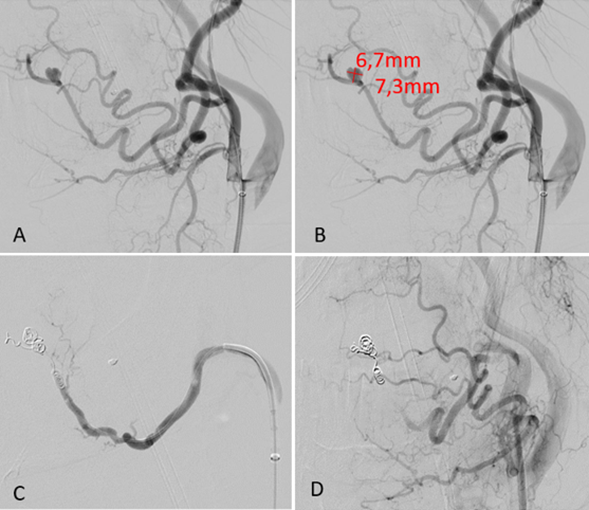

Clinical examination showed a large swelling, pushing the tongue cranially to the palate and the parapharyngeal space. CT-scan with IV contrast (Iodine) showed progressive active arterial bleeding of the left lingual artery (Figure 1).

Figure 1: CT scan. Active sublingual bleeding with contrast extravasation (blue arrows) and severe airway compression of the hematoma (red arrows) (axial, coronal and sagittal slices)